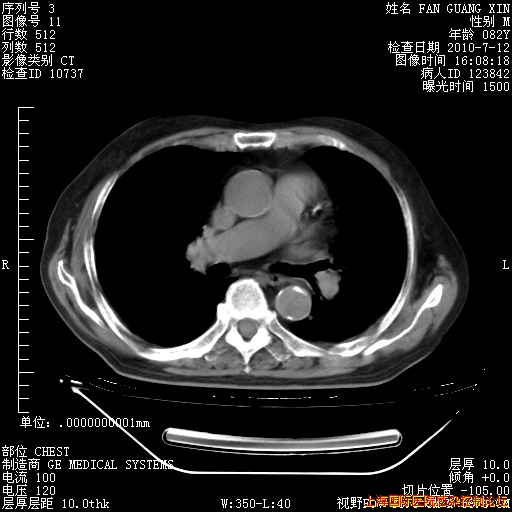

6月12日肺窗

回复